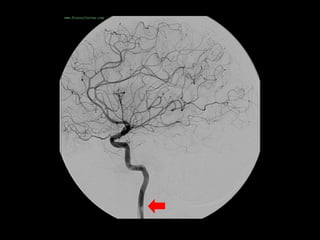

-Anterior temporal branch (best seen in AP view) , a typical

appearance of an anterior temporal branch of the MCA

proximal to the main bifurcation is indicated with the arrow